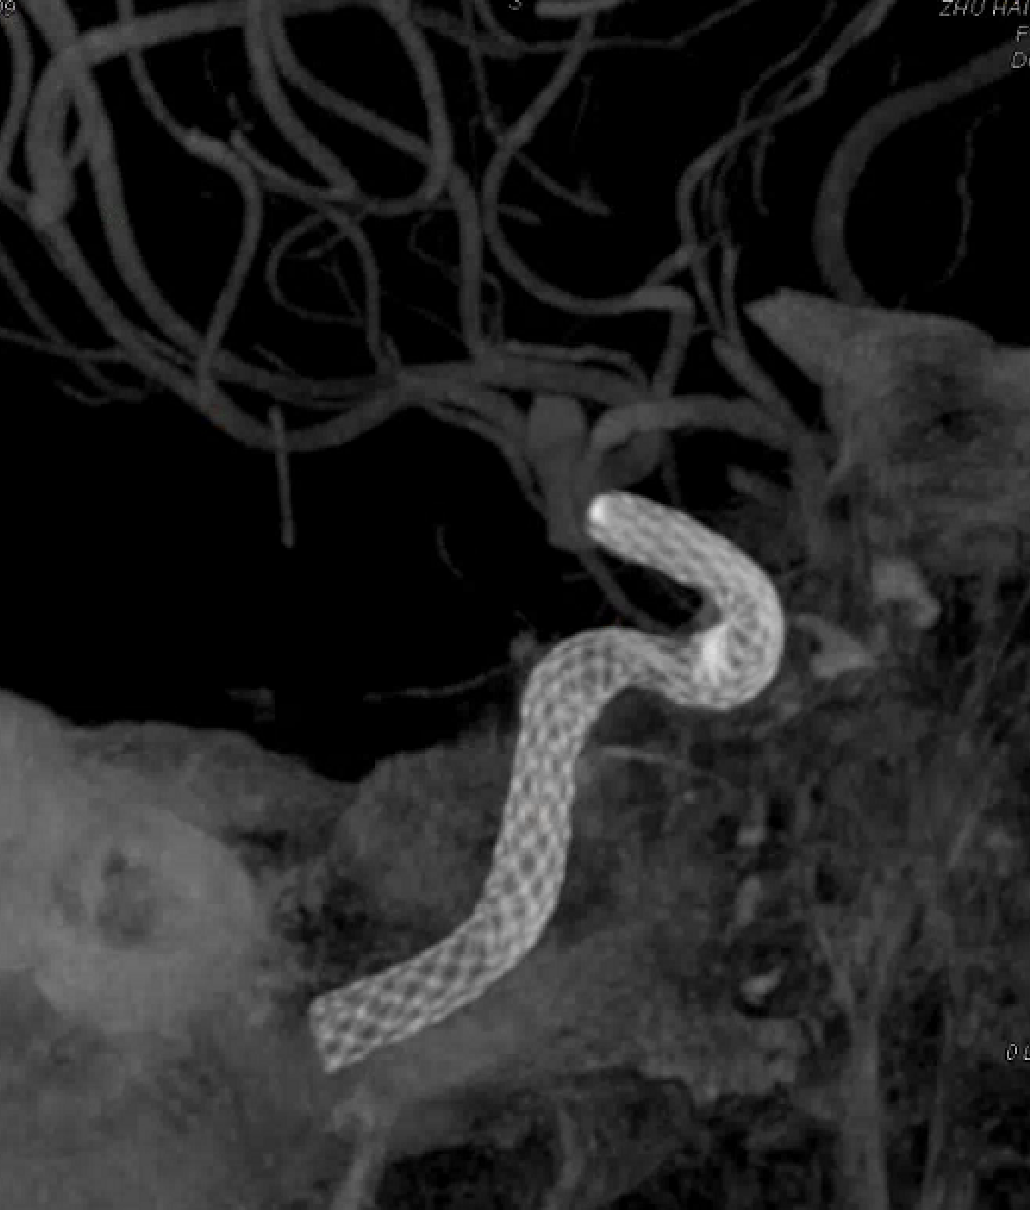

4mm×30mm Streamline

术后4月余随访:多发动脉瘤均未见显影,远端残余轻度狭窄

术前术后对比